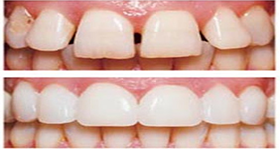

Veneers are thin ceramic shells bonded on to the surfaces of minimally prepared teeth. Veneers can correct or camouflage severe discoloration, chipped teeth, gaps between teeth and malpositioned teeth. Two or three visits are all it takes for a complete Smile Makeover. You will also be evaluate the final result before the start of veneer treatment with a mock up smile makeover. Veneers can only be done when there is adequate natural tooth structure remaining for cementation of the veneers